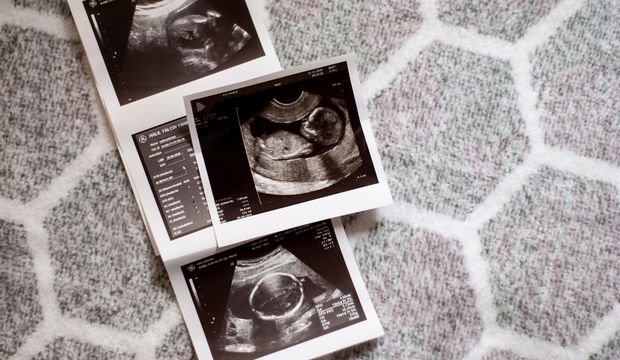

Belli aralıklarla gittiğiniz kontrollerde doktorlar bebeğinizin gelişimine ultrason ile bakar. Boyu, kilosu, tahmini doğum zamanı, kafa ve karın çevresi gibi bebeğinizin sağlığı hakkında pek çok bilgi verir. Bu bilgiler ise ultrason kağıdında kısaltmaları, değerleri ile birlikte yazmaktadır. Peki ultrason kağıdındaki bu kısaltmalar nedir ve bu terimler ne anlama gelmektedir?